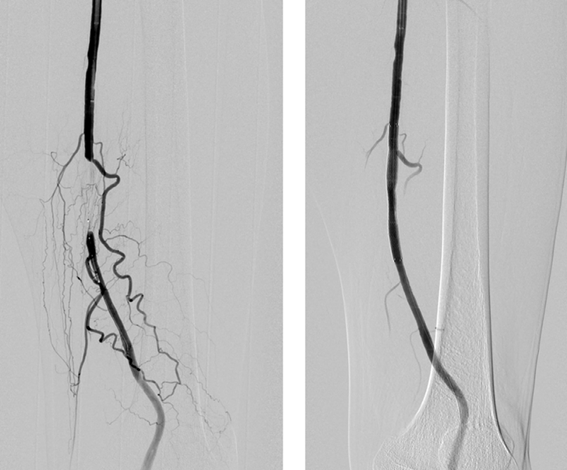

症状が強い場合には治療が必要になります。まずはお薬の治療、そして運動療法を行います。運動は足が少し痛いと感じる程度の運動を週に3回以上行うことが推奨されています。しかしそれでも症状が改善しない場合や指先が壊死・壊疽に陥ってしまうような場合には、詰まってしまっている血流を改善するためにカテーテル治療かバイパス術を行います。どちらを行うかはどの程度詰まっているのかということや、年齢を含めた全身的な状態で判断されます。

図にあるのは詰まってしまった太ももの動脈(大腿動脈)に対してカテーテル治療を行ったものです。